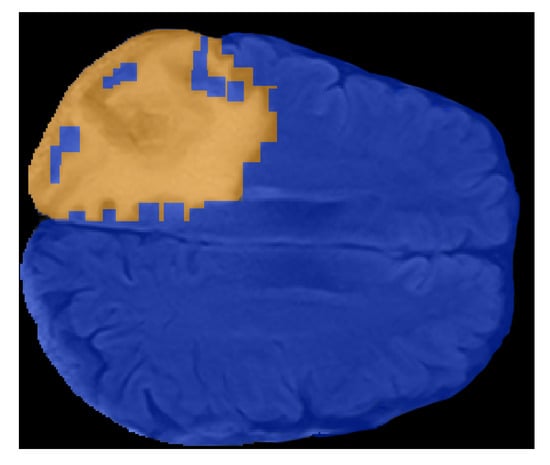

2.3. FLAIR Preprocessing

- FLAIRs were optimized by removing fat tissues and by performing skull stripping. The preprocessing steps, namely the removal of fat tissues and skull stripping, were performed by using the deep-learning algorithm described in Reference [52] (https://github.com/JanaLipkova/s3).